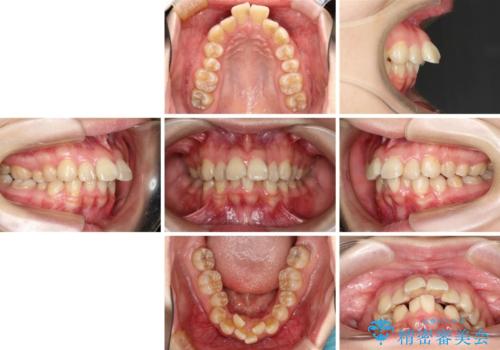

飛び出した前歯を引っ込めたい 目立たないワイヤーでの抜歯矯正

- 口元の閉じにくさと、前歯のでこぼこの歯並びを気にして来院された患者様です。

口元を積極的に引っ込めるために、上下左右の小臼歯計4本を抜歯することとしました。

咬み合わせが深く、咬合力強いため、補助装置を使用しながら積極的に口元を下げることとしました。